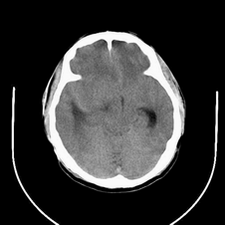

标题: CT25808:男,48岁,头痛多年,近段时间头痛加重伴步态不稳 [打印本页]

标题: CT25808:男,48岁,头痛多年,近段时间头痛加重伴步态不稳

平扫:右颞顶叶病灶呈等低密度伴大面积水肿,脑室受压变形。增强:病灶显著强化。考虑淋巴瘤或黑色素瘤。